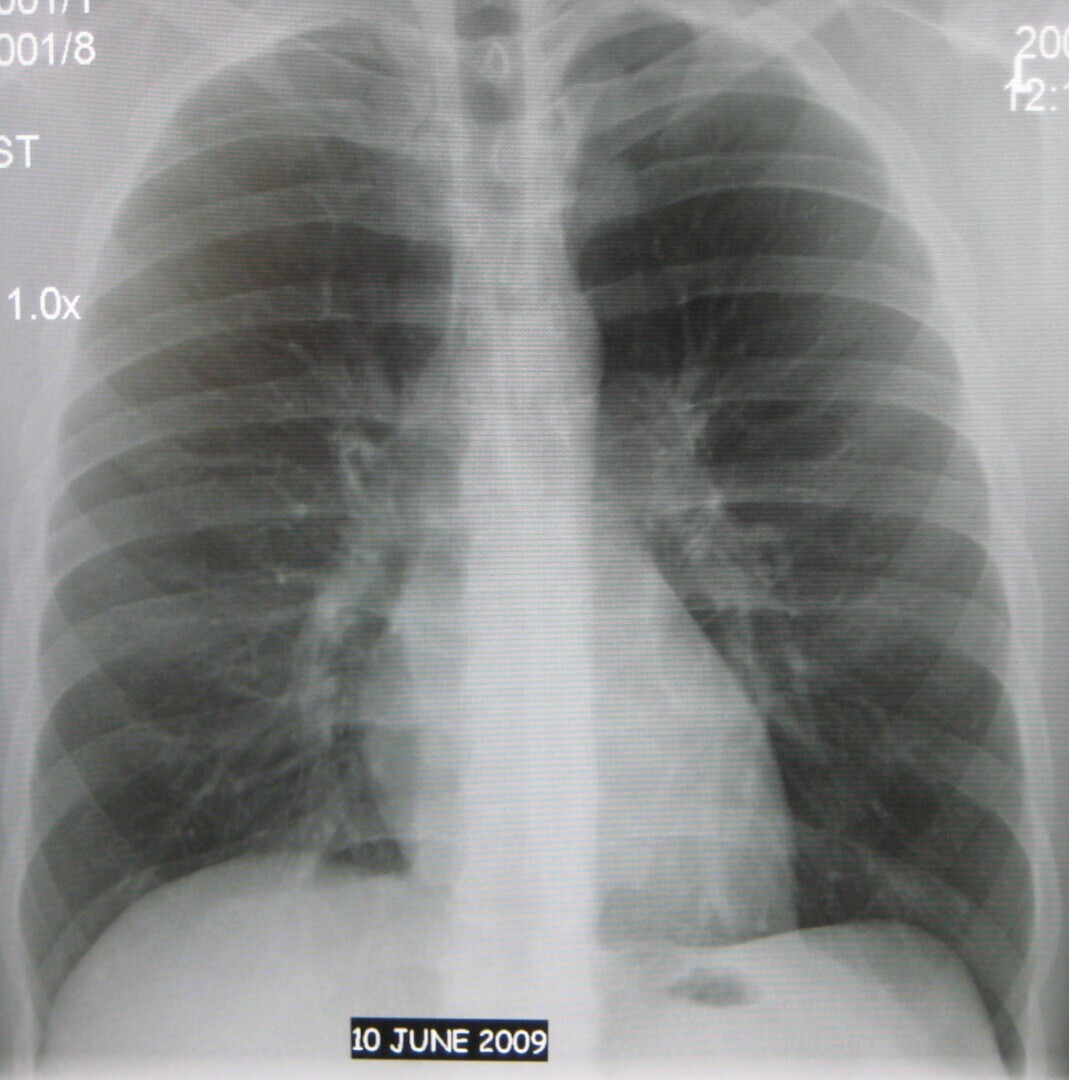

Анализы сдаются с целью своевременного выявления у пациента потенциально опасных заболеваний, которые могут угрожать жизни и здоровью, прежде всего, поражая лёгочную систему. Эти болезни зачастую длительное время протекают бессимптомно, что затрудняет их раннюю диагностику без использования специальных методов исследования.

На стадии средней тяжести или при тяжёлой форме заболевания у пациентов обычно появляются такие симптомы, как одышка, кашель, а также значительное снижение массы тела. Регулярная сдача анализов позволяет своевременно зафиксировать любые отклонения от нормы и начать соответствующее лечение.

Рентгенологическое исследование является эффективным методом диагностики, позволяющим выявить наличие раковых опухолей и туберкулёза. При обнаружении туберкулёза важно учитывать, что на ранних стадиях заболевание не представляет опасности для окружающих, но при переходе к более поздним стадиям пациент становится источником инфекции и способен заразить других людей. Согласно статистическим данным, один больной может инфицировать до 15 человек из своего окружения.(Р.Б.)